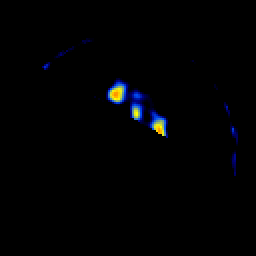

SPECT TL Study #5 -- Slice #53

[Home][Help][Clinical][Tour 1][Tour 2][Tour 3] Slice 53